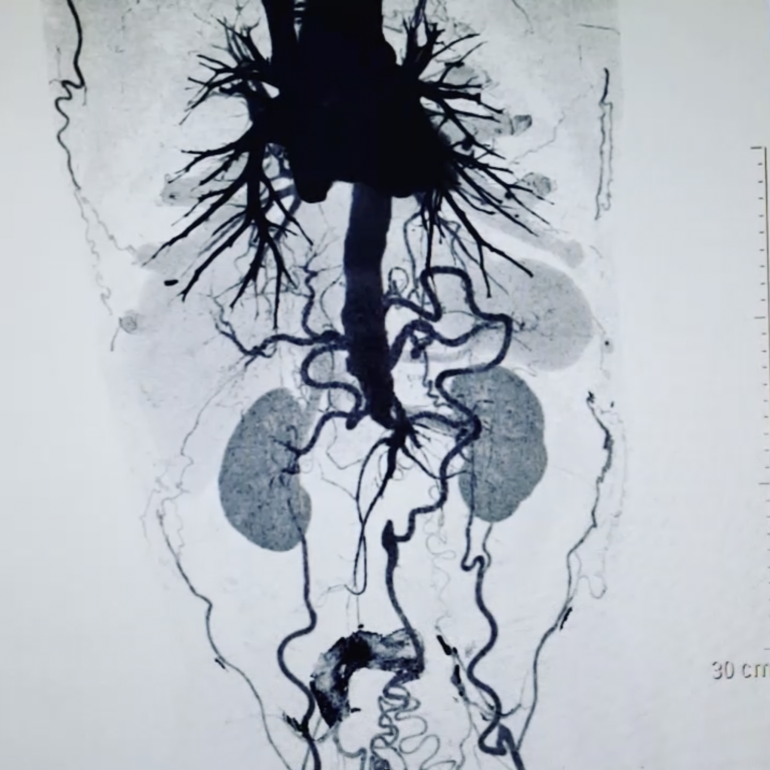

La diagnosi del disturbo viene normalmente posta a seguito di esecuzione di una TAC Addome con mezzo di contrasto o tramite una risonanza magnetica (RM). L'ecografia addominale non sempre sembra avere una capacita di discriminazione sufficiente per cogliere gli aspetti salienti della sindrome, anche se l'ecocolor doppler può essere utile nel dimostrare l'assenza di flusso vascolare all'interno delle arterie iliache.